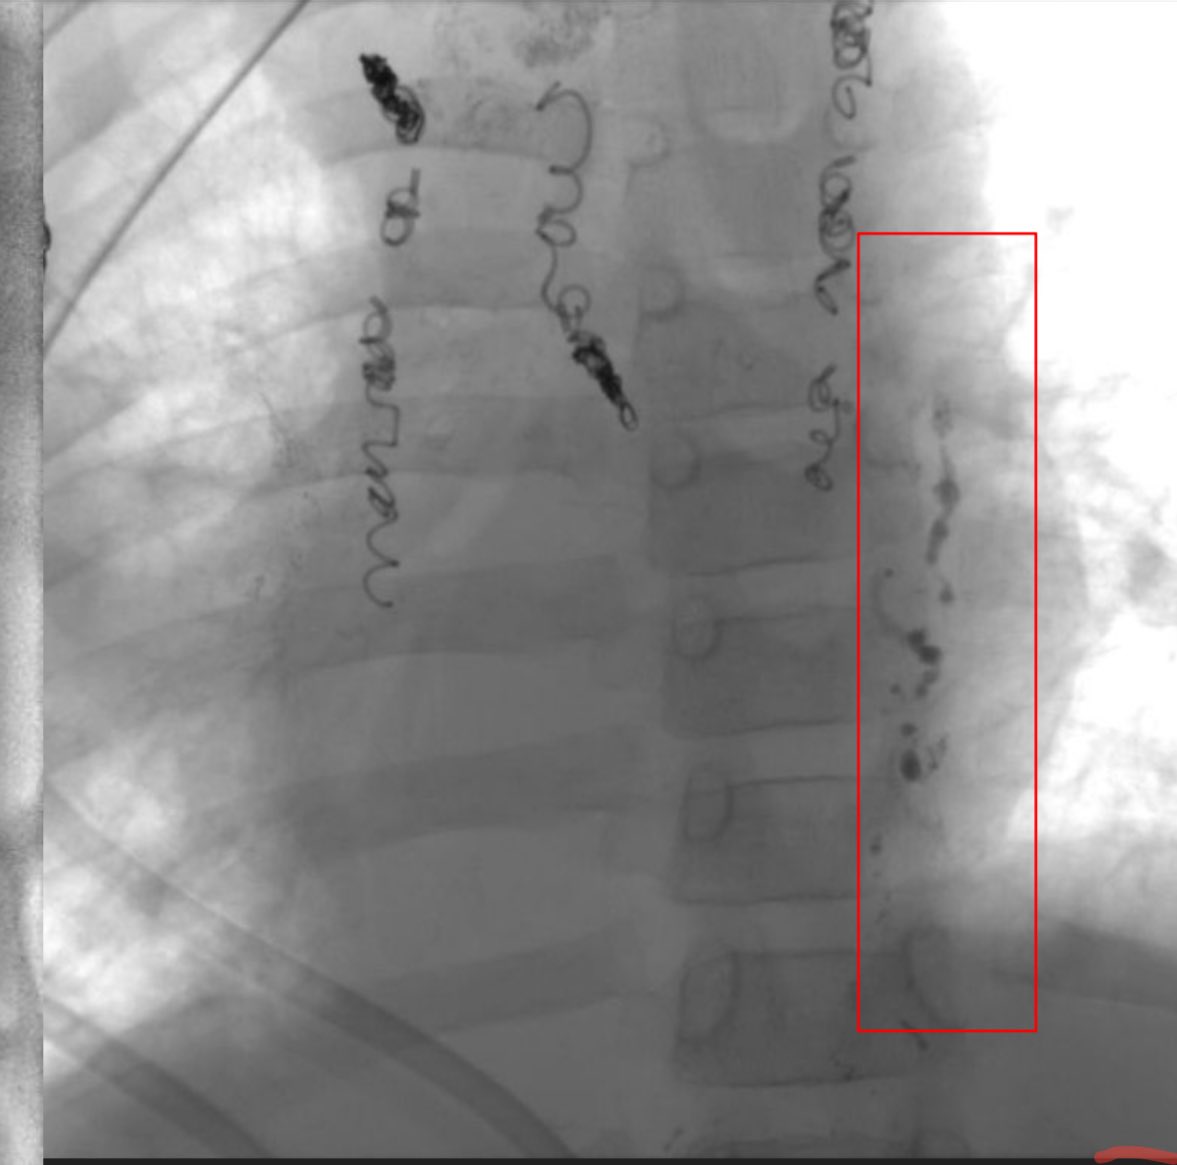

Centro interdisciplinario de anomalías vasculares CIAV del sanatorio Materdei, un orgullo formar parte de este equipo . Consultas ciavmaterdei@gmail.con #anomaliasvasculares #hemangiomas

Pediatric Interventional Radiologist. #pedsir #vascularanomalist #Anomaliasvasculares. Chief of Clinic at Garrahan Hospital and Materdei Clinic @PEDimage